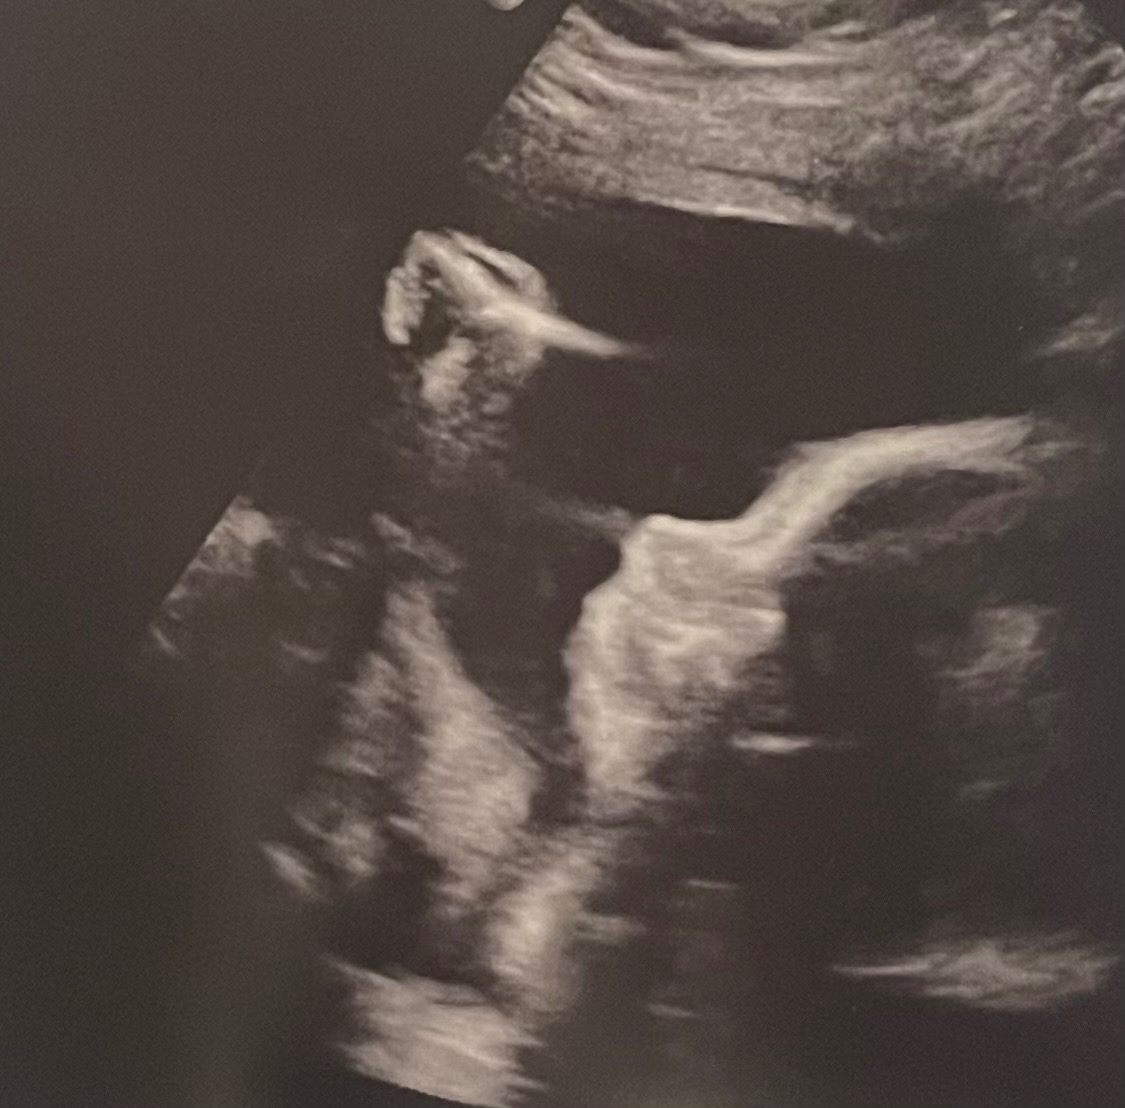

Hi, I’m Jack, and my amazing wife Alicia is now 31 weeks pregnant with our daughter, Sophia Grace. What started as a joyful ultrasound visit, so Alicia’s mom (visiting from California) could see her grandbaby, turned into an unexpected diagnosis at 27 weeks: duodenal atresia, a blockage in Sophia’s small intestine (the “double bubble” sign on MRI).

The great news? Our detailed fetal MRI at Cincinnati Children’s confirmed everything else is perfect; heart, lungs, brain, eyes, spleen, limbs, and strong growth. Genetic testing came back low risk for Down syndrome and other conditions. Sophia is a fighter, and we’re so grateful.